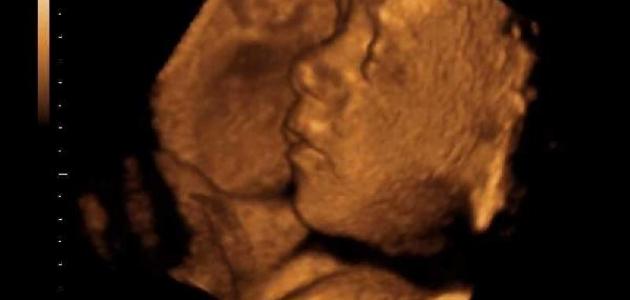

يتم إجراء هذا الفحص في الأسبوع السادس من الحمل، وهو فحص يهدف لتحديد مدى سلامة الحمل، ومن خلاله يتم الكشف عن احتمالية تعرض الجنين للتشوّهات، أو أي خلل في نموّه السليم، بحيث يتمّ سماع نبضات قلبه.

يجرى هذا الفحص في الأسبوع العشرين من الحمل، بهدف الكشف عن إصابة الجنين بالتشوهات، وبالعيوب الخلفية، ويتم هذا الفحص عن طريق الأمواج فوق الصوتية.